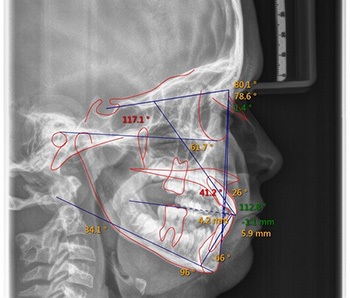

An 11-year-old patient was referred by a pediatric dentist for orthodontic evaluation with several unusual findings: microdontia, severe developmental delay in eruption, and several positional concerns. Clinical and radiographic examination revealed a retained tooth in the upper right quadrant, suspected to be either a primary tooth or a supernumerary permanent lateral. The upper right first molar was ectopic, appearing to be “caught” beneath the retained tooth, and the upper left first molar had not erupted at all. Additional findings included a full posterior right crossbite and evidence of overall dental delay compared with age norms (Figs. 1–3).

Fig. 2